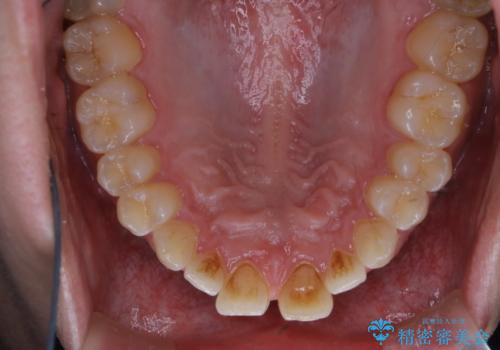

矯正を考えている方のPMTC

治療症例の内容

- 20代男性

- 1日

- 1回

- 矯正治療を考えていて、歯科医院が久しぶりのためまずはクリーニングしたいとのことでした。PMTC60分コースを行いました。

- 1万円+tax費用は治療当時の料金となります